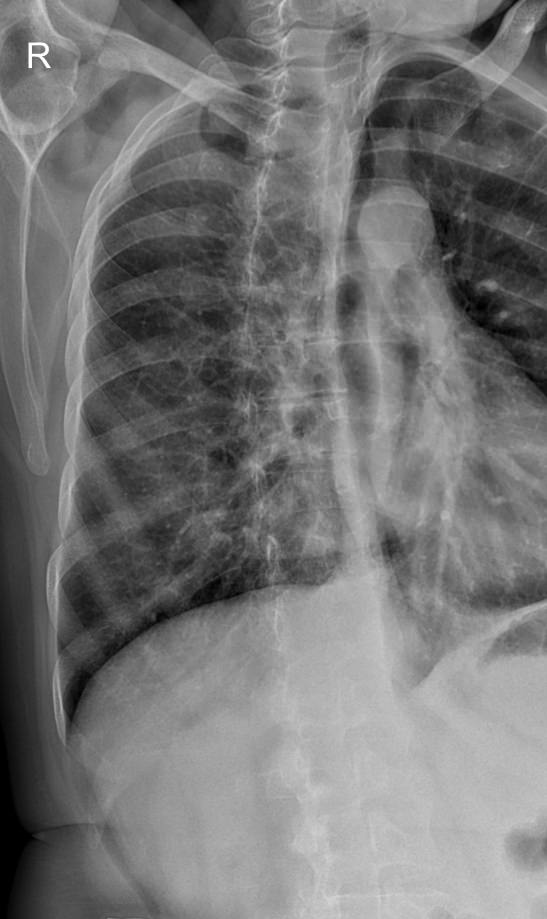

В качестве основного метода исследования при патологии ребер назначают рентгенодиагностику. Это простой и доступный способ узнать состояние костной ткани изнутри, не нарушая целостности кожных покровов. минимальная доза излучения современных рентгеновских аппаратов делает рентгенографию безопасной.

Что покажет рентген ребер (прицельно)

На рентгенограмме будут видны:

• Перелом и его локализация;

• Отек, отломки и осколки кости и инородные тела в мягких тканях;

• При рентгене верхних ребер ― возможные повреждения тканей легких, трахеи, пищевода;

• При обследовании нижних ребер ― повреждение тканей и органов верхней части живота: печени, селезенки, почек, диафрагмы.